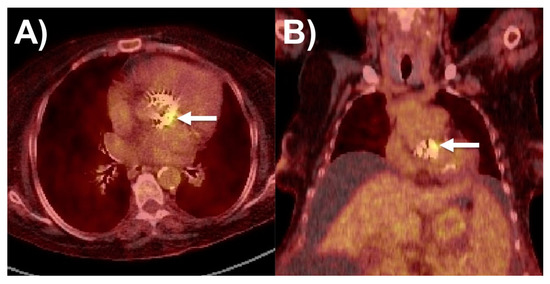

6.1. 18F-FDG PET/CT

- Wang, T.K.M.; Sánchez-Nadales, A.; Igbinomwanhia, E.; Cremer, P.; Griffin, B.; Xu, B. Diagnosis of Infective Endocarditis by Subtype Using 18F-Fluorodeoxyglucose Positron Emission Tomography/Computed Tomography: A Contemporary Meta-Analysis. Circ. Cardiovasc. Imaging 2020, 13, e010600. [Google Scholar] [CrossRef] [PubMed]

- Saby, L.; Laas, O.; Habib, G.; Cammilleri, S.; Mancini, J.; Tessonnier, L.; Casalta, J.P.; Gouriet, F.; Riberi, A.; Avierinos, J.F.; et al. Positron emission tomography/computed tomography for diagnosis of prosthetic valve endocarditis: Increased valvular 18F-fluorodeoxyglucose uptake as a novel major criterion. J. Am. Coll. Cardiol. 2013, 61, 2374–2382. [Google Scholar] [CrossRef] [PubMed]

- Mahmood, M.; Kendi, A.T.; Ajmal, S.; Farid, S.; O’Horo, J.C.; Chareonthaitawee, P.; Baddour, L.M.; Sohail, M.R. Meta-analysis of 18F-FDG PET/CT in the diagnosis of infective endocarditis. J. Nucl. Cardiol. 2019, 26, 922–935. [Google Scholar] [CrossRef] [PubMed]

- Juneau, D.; Golfam, M.; Hazra, S.; Erthal, F.; Zuckier, L.S.; Bernick, J.; Wells, G.A.; Beanlands, R.S.; Chow, B.J. Molecular Imaging for the diagnosis of infective endocarditis: A systematic literature review and meta-analysis. Int. J. Cardiol. 2018, 253, 183–188. [Google Scholar] [CrossRef]